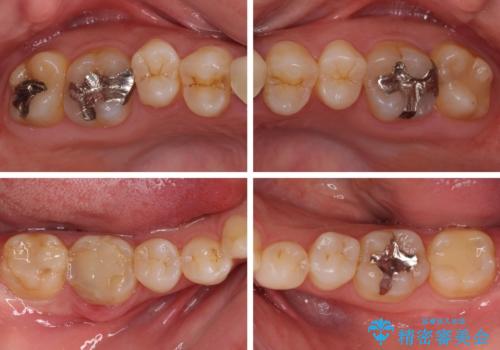

- 審美的ではない上の前歯とデコボコの下の前歯、歯茎が腫れている奥歯を気にして来院された患者様です。

根管治療の必要な歯がいくつかあるため、まずは根管治療を行い、その後インビザラインにて矯正治療を行うこととしました。

矯正治療後に前歯をセラミックブリッジに、奥の銀歯はセラミックインレーやPGAインレー(ゴールドインレー)にて補綴・修復治療を行うこととしました。